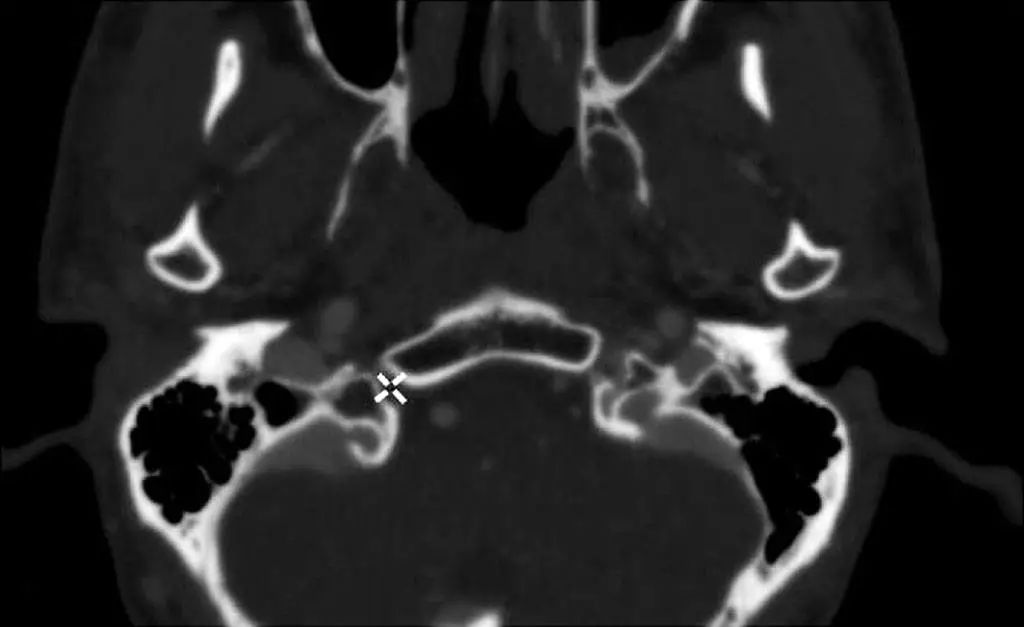

图2-18 舌下神经管(CT骨窗,白色+字)